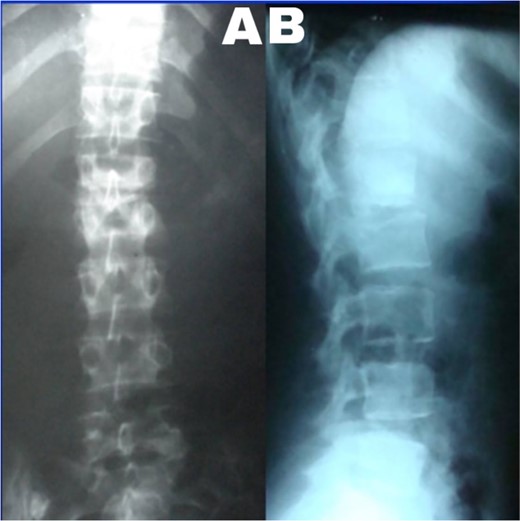

A 24-year-old farmer female was admitted to the Department of Neurosurgery with low back pain, no fever, cough, motor deficit, or any symptoms. Medical, surgical, family histories and physical examinations were unremarkable. The laboratory findings showed a white cell count of 9.8 × 103/μL, C-reactive protein concentrations of 20, erythrocyte sedimentation rate of 50 mm/1 h, 90 mm/2 h and tuberculin skin test was positive. X-ray films showed the collapse of the L1, L2 vertebrae, and L1–2 intervertebral space (Fig. 1). An abscess was observed at the L1–L2 vertebral level in lumbar magnetic resonance imaging (MRI) (Fig. 2). Chest X-rays and Sputum smear were negative. The patient was treated with anti-TB treatment (Isoniazid, Rifampicin, Ethambutol, Pyrazinamide) due to spinal TB findings on MRI (Fig. 3). After 40 days, the patient was diagnosed with grade 1/5 lower limb weakness, and bladder and bowel dysfunction, with no impairment in sensation, which predicts spinal infection. MRI confirmed these abnormalities and showed typical findings such as vertebral endplate destruction, bone marrow and disk signal abnormalities, and paravertebral or epidural abscesses (Fig. 3). Due to clinical manifestations and MRI spinal TB findings (Fig. 3), the patient underwent surgical debridement, interbody fusion and internal fixation with fibular autografting and supplemental posterior spinal stabilisation using a posterior-only approach. On post-operative follow-up, the treatment continued for 9 months, in addition to physical therapy for lower limb weakness. In the end, the patient returned to full motion with grade 5/5 in the lower limb, normal sensation, and no bladder or bowel incontinence. No recurrence was observed in the grafting area. Radiologically 2, 6 and 12 months, 14 years’ post-operation, the patient had achieved full bony graft spinal fusion (Figs 4–6).

Sagittal T2-weighted MRI shows severe disco vertebral destruction, the formation of epidural abscess and compression of the spinal cord at the L1–2 level.

Lumbar T1 and T2 consistent with an abscess at the L1–2 vertebral level. (A) and (B) showed that the height of the L1 and L2 vertebral bodies was markedly reduced and the dural sac and spinal cord were severely compressed by an abscess posterior to the vertebral body. (C and D) Axial T1 shows a well-defined paraspinal abscess. The anterior epidural abscess compresses the spinal cord.